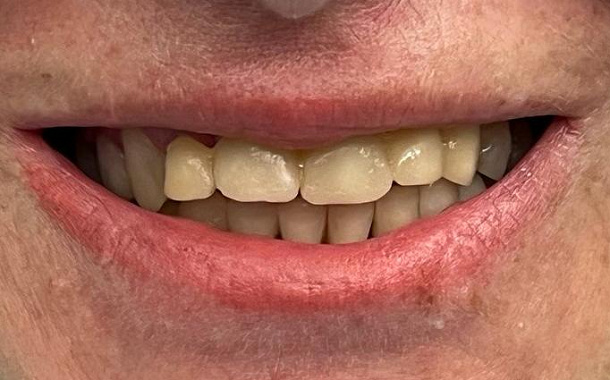

Полный прайс-листКейсы: до и после